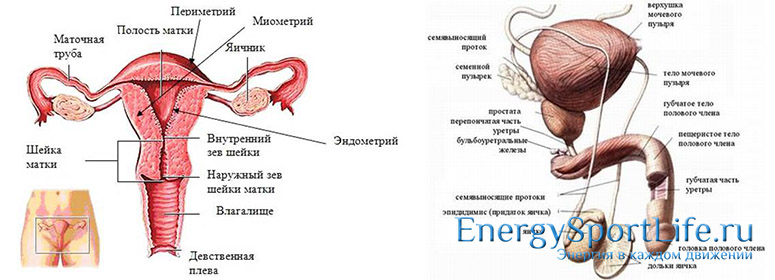

Репродуктивная система

Репродуктивная система спасает человеческий вид от вымирания. Мужские и женские органы размножения различны по своим функциям и строению.

Мужская половая система состоит из следующих органов :

— Семявыводящий проток;

— Уретра;

— Яичко;

— Придаток яичка;

— Половой член.

Строение женской половой системы кардинально отличается от мужской :

— Матка;

— Фаллопиева труба;

— Яичник;

— Шейка матки;

— Влагалище.

Мочеполовая система в анатомии тела человека

В некоторых научных источниках мочеполовую систему рассматривают как 2 составляющие: мочевыделительную и репродуктивную, однако, из-за тесной взаимосвязи и смежного расположения их всё же принято объединять. Строение и функции этих органов сильно разнятся в зависимости от половой принадлежности, поскольку на них возложен один из самых сложных и загадочных процессов взаимодействия полов — репродукция.

И у женщин, и у мужчин мочевыделительная группа представлена следующими органами:

Репродуктивная составляющая мочеполовой системы сильно разнится в зависимости от пола. Так, у мужчин она включает яички с придатками, семенные железы, простату, мошонку и пенис, которые в комплексе отвечают за формирование и эвакуацию семенной жидкости. Женская половая система устроена более сложно, поскольку именно на представительниц прекрасного пола ложится ответственность за вынашивание ребёнка. К ней относятся матка и маточные трубы, пара яичников с придатками, влагалище и наружные половые органы — клитор и 2 пары половых губ.